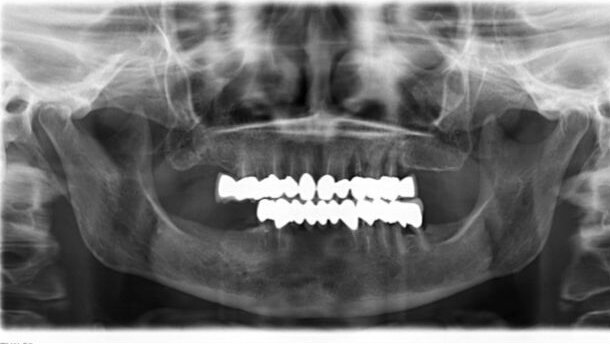

Situazione generale buona, nessuna sofferenza cardiovascolare e respiratoria. A livello della cavità orale la paziente è portatrice di una protesi fissa full arch su denti naturali, sia dell’arcata superiore che inferiore (Fig. 1). In zona 23-26 presenta una infiammazione acuta dei tessuti molli e la presenza di uno splint acrilico tra la protesi dell’arcata superiore in particolare in zona 22-23 (Figg. 2, 3).

Dopo circa 6 mesi, è stato effettuato un controllo clinico e radiografico, (Figg. 25, 26), e sono state prese le impronte di precisione con materiale polietere andando a realizzare gli elementi definitivi su pilastri Syncone, DENTSPLY Implants, su entrambe le arcate in metallo-ceramica (Figg. 27-34).

Dall’esame radiografico e clinico si può affermare che entrambe le procedure chirurgiche hanno consentito di ottenere un’ottima osteointegrazione e che la presenza di una costante somministrazione di corticosteoidi non ha influito sul risultato finale. Inoltre, è emerso che non vi è differenza tra le due procedure di carico, in quanto i risultati clinici e radiografici sono sovrapponibili.